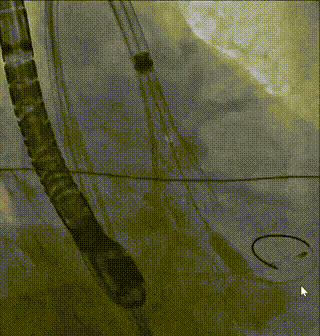

完全释放

最终造影1

最终造影2

术后即刻超声,瓣膜与患者自身解剖结构贴合良好,无瓣周漏,跨瓣压差降为3mmHg,峰值流速降为1.32m/s,手术取得圆满成功。